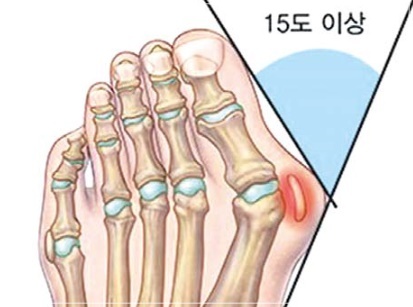

무지외반증은 엄지발가락이 둘째발가락 쪽으로 심하게 휘어져 엄지발가락 관절이 안쪽으로 돌출된 상태를 말하며, 심한 경우에는 엄지발가락이 둘째발가락과 엇갈리는 정도까지 돌아가기도 합니다. 특히 앞이 좁고 굽이 높은 신발을 자주 신는 여성에 흔한 대표적인 족부 질환입니다.

무지외반증 여부의 진단은 시진과 촉진(발가락 모양, 굳은살 등)으로 가능하지만 치료 방침을 결정하기 위해서는 방사선 검사가 필요합니다. 뼈와 뼈가 이루는 각도, 관절의 변형과 염증, 운동 범위 등을 측정합니다.